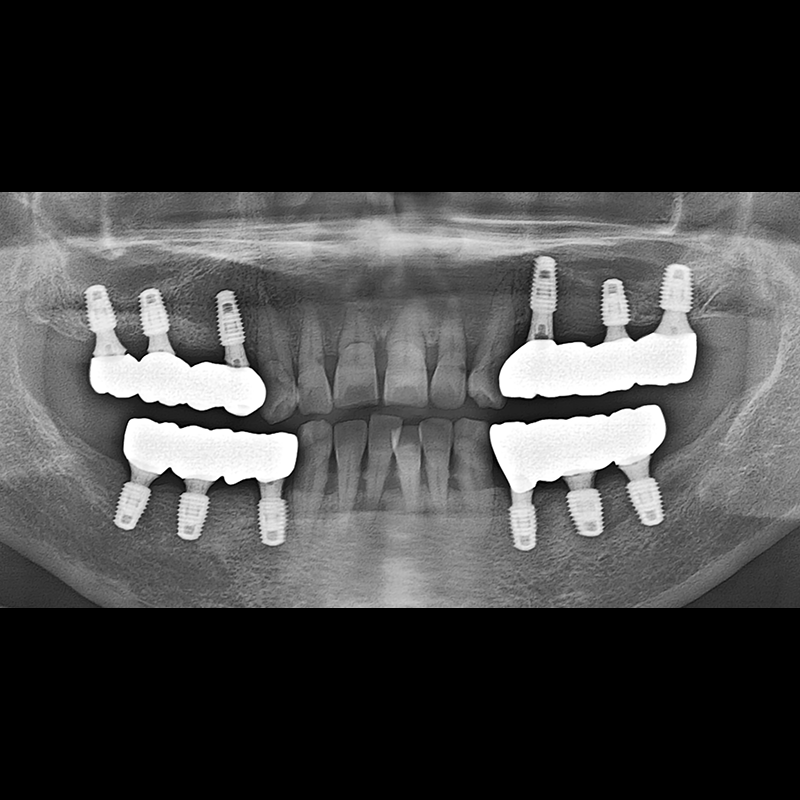

IMPLANT

BEFORE AFTER

种植牙前后的照片 2025.05.30

在缺失的牙齿部分和难以挽救的牙齿位置植入了种植牙。